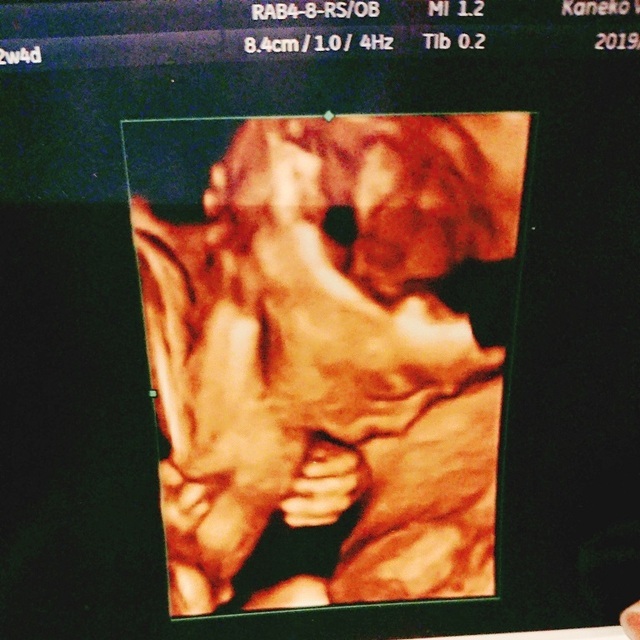

22週3日(22w3d・男の子)|N氏 さん(26歳)

エコー写真撮影時のエピソード:

今回、初めての子で4Dエコーをしてもらって、この時旦那さんも一緒だったんですが、顔を見せてくれてとてもかわいいし、愛おしく思いました。

この時に性別も男の子かも?と言われて、旦那さんは男の子希望だったので喜んでいました。 あんなに小さかった子が大きくなって、 今は人間らしい姿になっていて、 ほんとに凄いなと感激しました。

私は正直、女の子希望だったのですが、 母子ともに健康で生まれてきてくれればどちらでもいいと思いましたし、 私達の子どもにはかわりないので今は早く会いたいなと毎日胎動を感じながら、日々を過ごしています。

両親、兄姉、親戚、皆楽しみにしてくれているので残り少ないマタニティライフを楽しみつつ、旦那さんとの2人の時間を大切にして、出産にのぞみたいと思っています。 それまで準備などをして、我が子の誕生を待ちたいと思ってます。